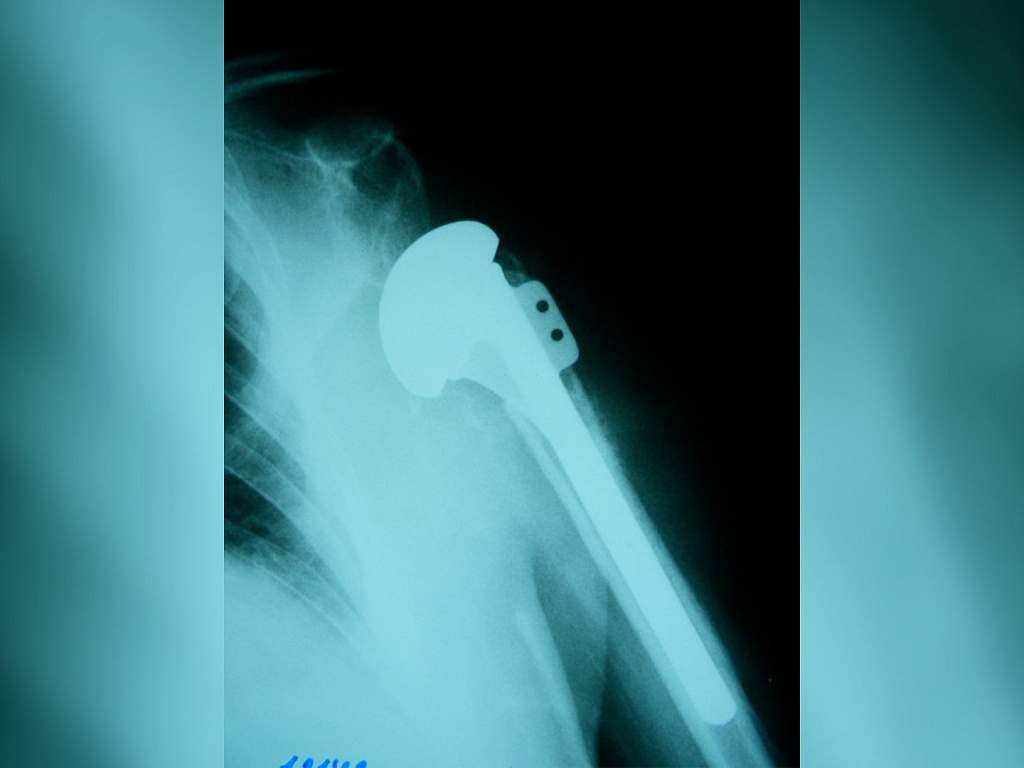

Реверсивное эндопротезирование

Реверсивное эндопротезирование 132 фото